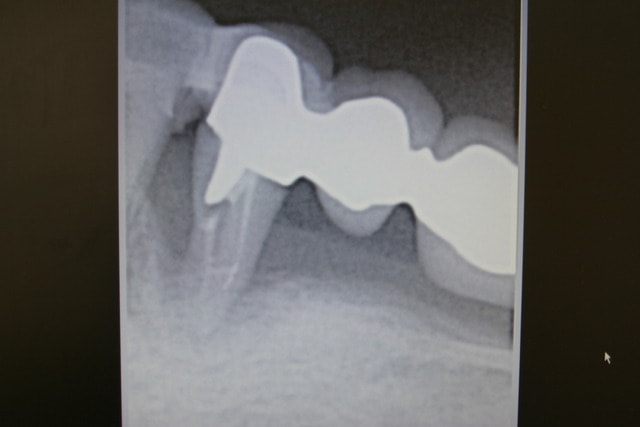

patiente du sud de l'espagne 75 ans, qui présente une mobilité importante de son bridge secteur 3, associé à un problème paro général, après contention de ce bridge avec fibres de verre imprégnées, et traitement BOST , 4mois plus tard l'os réapparait ...le traitement à eu lieu avril 2009 le contrôle radio JUIN 2009;